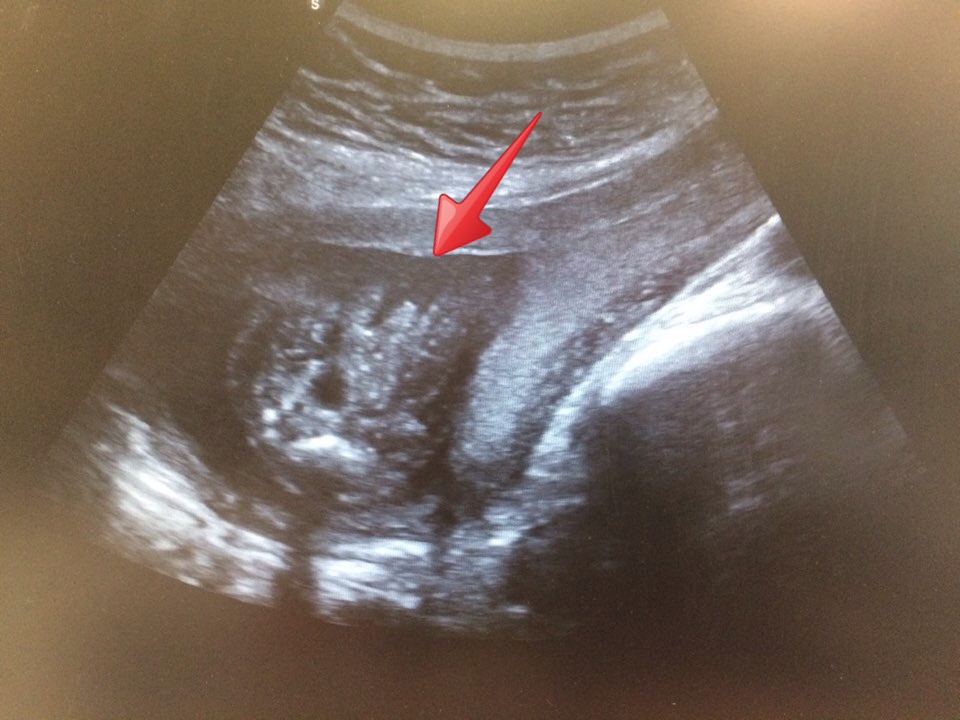

I went through her pictures and the only possible potty shot is this. Doesn't really look like the general ones though so I'm posting for help.

Is this a potty shot(and a penis)? Or is it the heart or the brain or whatever else part of the body?